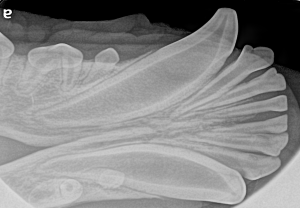

Feline Full Mouth Radiograph example